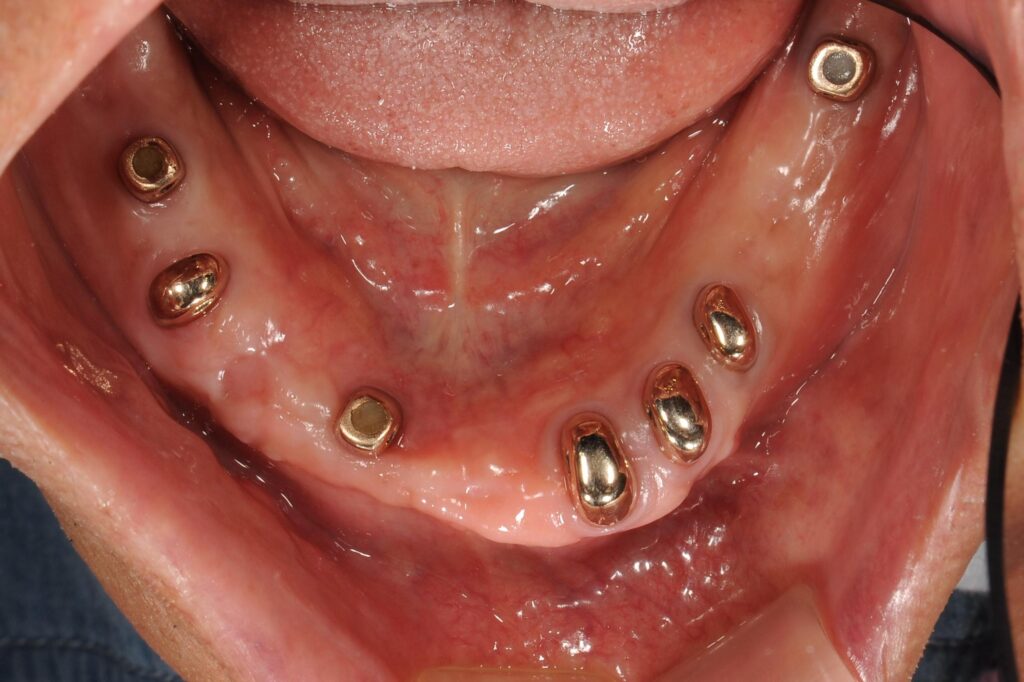

【治療終了時の類似例】

いかがでしょうか。

この治療法のメリットは・・・

①取り外しの入れ歯なので入れ歯を外せば清潔に歯磨きができる

②多数のインプラントは必要ない。実際、今回治療をされている患者様は1本のインプラントのみ使用。

③硬いものも食べることが可能で、食事や会話の際に外れることはない。